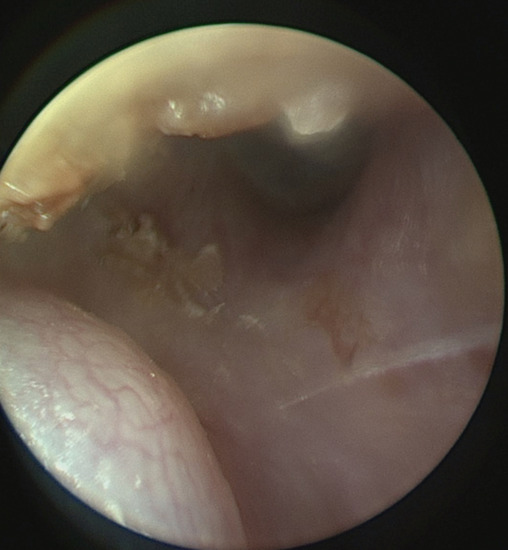

| Our case | 1/87/f | posterior | A | 13 × 10 × 6 mm | End-Exc | No rec |